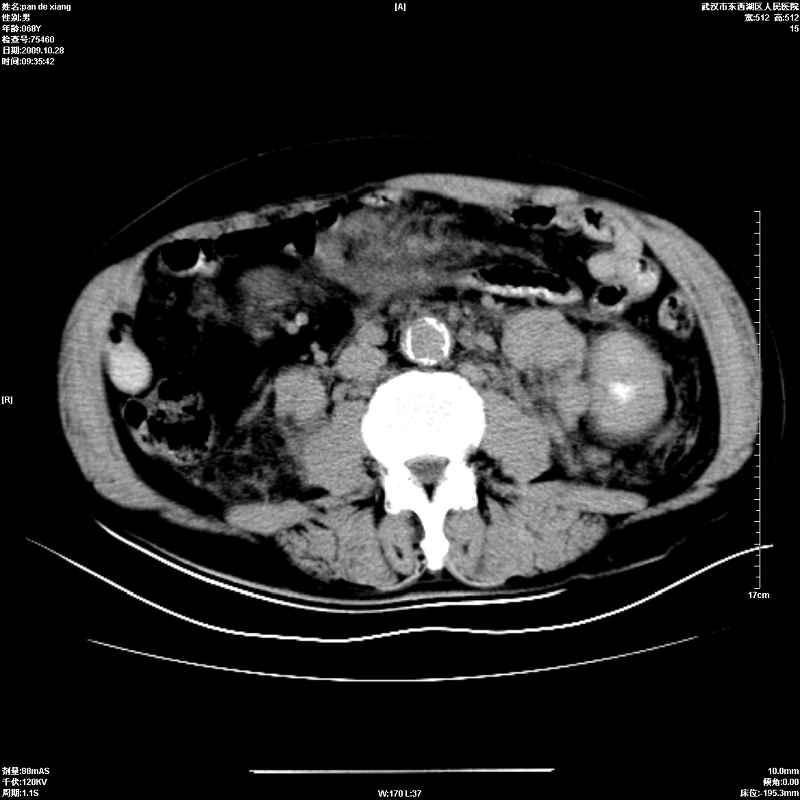

以下是引用杀毒软件在2009-10-28 20:41:00的发言:[br]结合临床考虑---白血病双肾改变或淋巴瘤。

以下是引用zxl51642在2009-10-29 9:59:00的发言:[br]结合临床“单克隆免疫球蛋白血症”,考虑双肾为继发损害并肾功能不全(尿中大量igg及少量iga、igm等大分子免疫球蛋白滤出所致继发损害),椎前软组织肿块为髓外造血。与浆细胞瘤有区别,平扫时有战友说的很清楚。